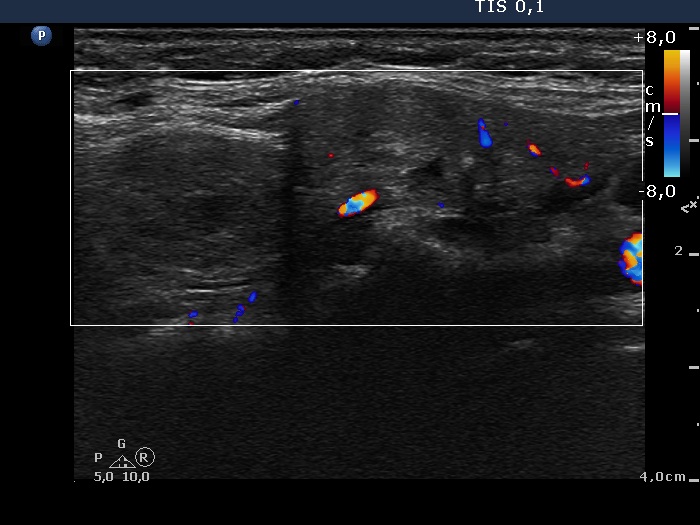

The operated thyroid - Case 18. Recurrent nodules in aberrant location

(ultrasonographic picture 5)

Upper and lateral to the left lobe, longitudinal scan, color Doppler mode. The vascularization is not specific.